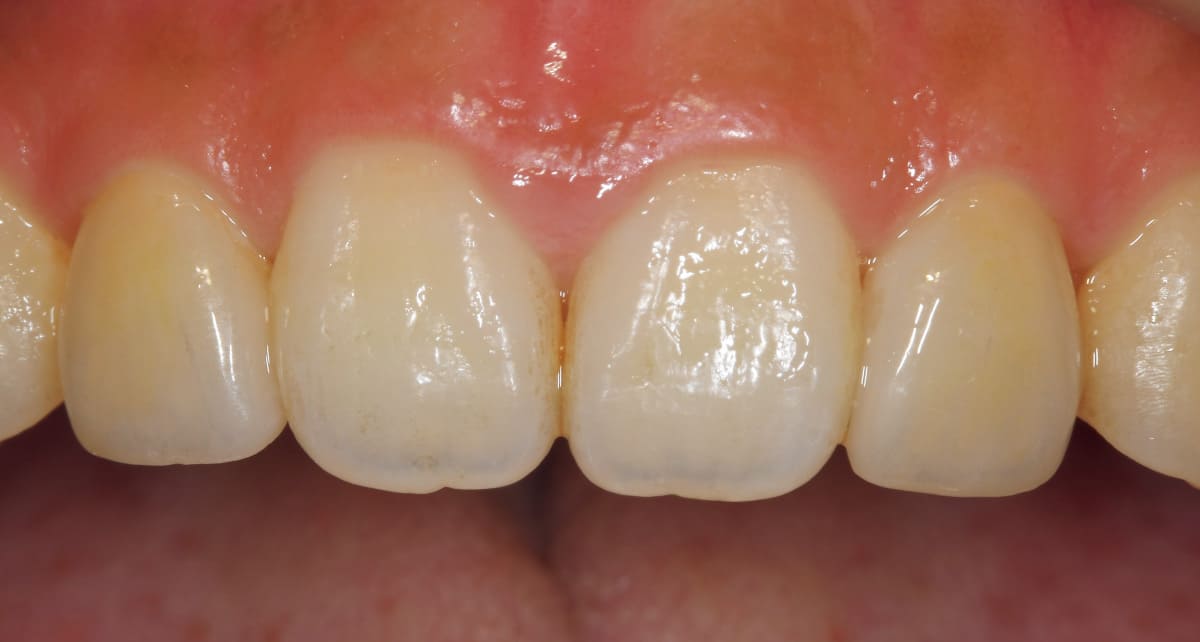

ダイレクトボンディング|ペースト状の材料を歯に盛り付けるだけ。

Before

After

むし歯や前歯の隙間、欠けた歯を修復する治療。セラミックとプラスチックの混合物であるレジンというペースト状の材料を直接歯に盛り付ける。クラウンのように型取りする必要もないので短期間で済み、歯を削る範囲も最小限。

【料金】3万円〜

【治療期間】1日〜2週間程度